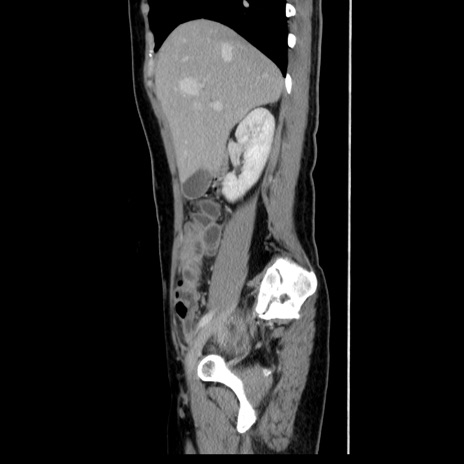

症例39(矢状断像)

【症例】40歳代女性

【主訴】上下腹部痛

【現病歴】2日目から下腹部痛あり。夜間は痛みで眠れなかった。昨日より上腹部痛と下痢が出現。臥位で痛みは軽快したため、休んでいた。本日になって臥位でも立位でも痛みが強くなってきたため救急要請。

【既往歴】子宮内膜症

【身体所見】部:平坦・軟、左上下腹部に圧痛あり、反跳痛あり。

【データ】WBC 21800、CRP 26.78

CT